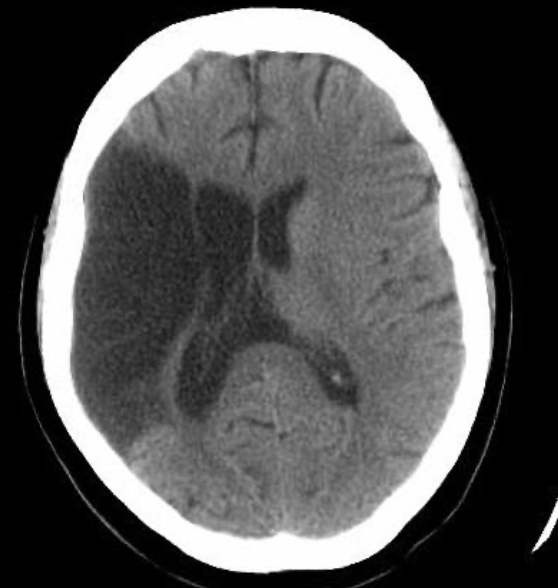

16

Q

A

EVC hemorragico

Hipertensivo